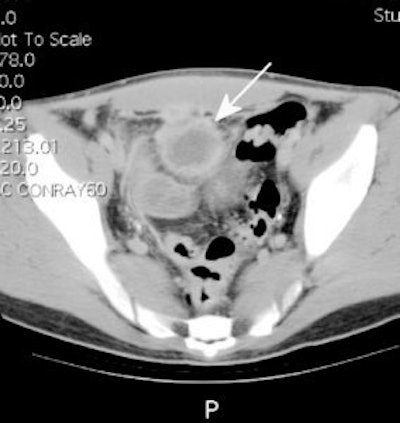

Crohns disease with abscess: The patient below had Crohns disease and was being evaluated for persistent fevers and elevated white blood cell count. The In111-WBC exam demonstrated a very intense focal accumulation of labeled WBC's in the mid pelvis (black arrow). Large bowel activity can also be seen, however, these images were performed at 24 hours following injection and cells sloughed from sites of active inflammation can be carried distally causing the appearance of colitis. The CT scan (right) had actually been performed prior to the white blood cell study and had been interpreted as negative for abscess. In retrospect, the abscess can be seen on the CT scan (white arrow), but was missed because of poor bowel opacification. Click CT to view more images. |

|